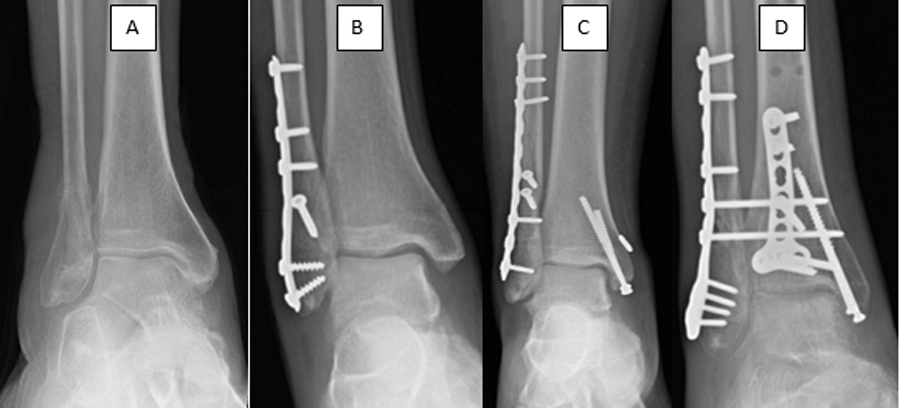

Ankle fractures manifest in various forms, each affecting different components of the ankle joint. Common types include lateral malleolus fractures, medial malleolus fractures, bimalleolar fractures, trimalleolar fractures, pilon fractures, and syndesmotic injuries. The complexity of the fracture dictates the course of treatment and recovery duration.

Treatment for ankle fractures depends on factors such as the type and severity of the injury. While some fractures may heal with conservative measures like immobilization with braces or casts, others necessitate surgical intervention. Reduction, a procedure involving the realignment of fractured bones, may be performed under local anaesthesia to facilitate proper healing.